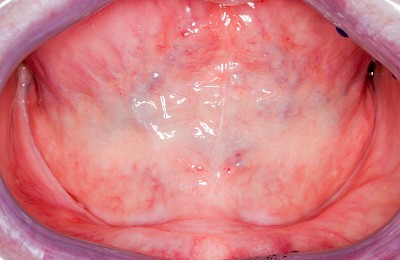

Lippen-Kiefer-Gaumenspalte

Lippen-Kiefer-Gaumenspalten (LKG-Spalte) sind angeborene Fehlbildungen im Mund-Kiefer-Gesichtsbereich. Die Gewebestrukturen im Bereich des Oberkiefers sind im Zuge der Entwicklungen bis zur Geburt nicht zusammengewachsen. Diese Fehlbildung zählt zu den häufigsten Fehlbildungen des Menschen, von 500 Neugeborenen ist eines betroffen. Die Fehlbildungen können sich auf Lippe, Gaumen und Kiefer allein beschränken, treten häufig aber kombiniert und in seltenen Fällen sogar beidseits auf.

Heute werden in Deutschland Menschen mit Lippen-Kiefer-Gaumenspalten bereits ab Geburt von Experten verschiedener Fachrichtungen (Mund-Kiefer-Gesichtschirurgen, Kieferorthopäden, Logopäden) betreut, damit entsprechende Korrekturen schon frühzeitig erfolgen können. Gerade jedoch bei älteren Menschen ist dies nicht immer geschehen. Diese Menschen tragen häufig technisch aufwendige Zahnprothesen.